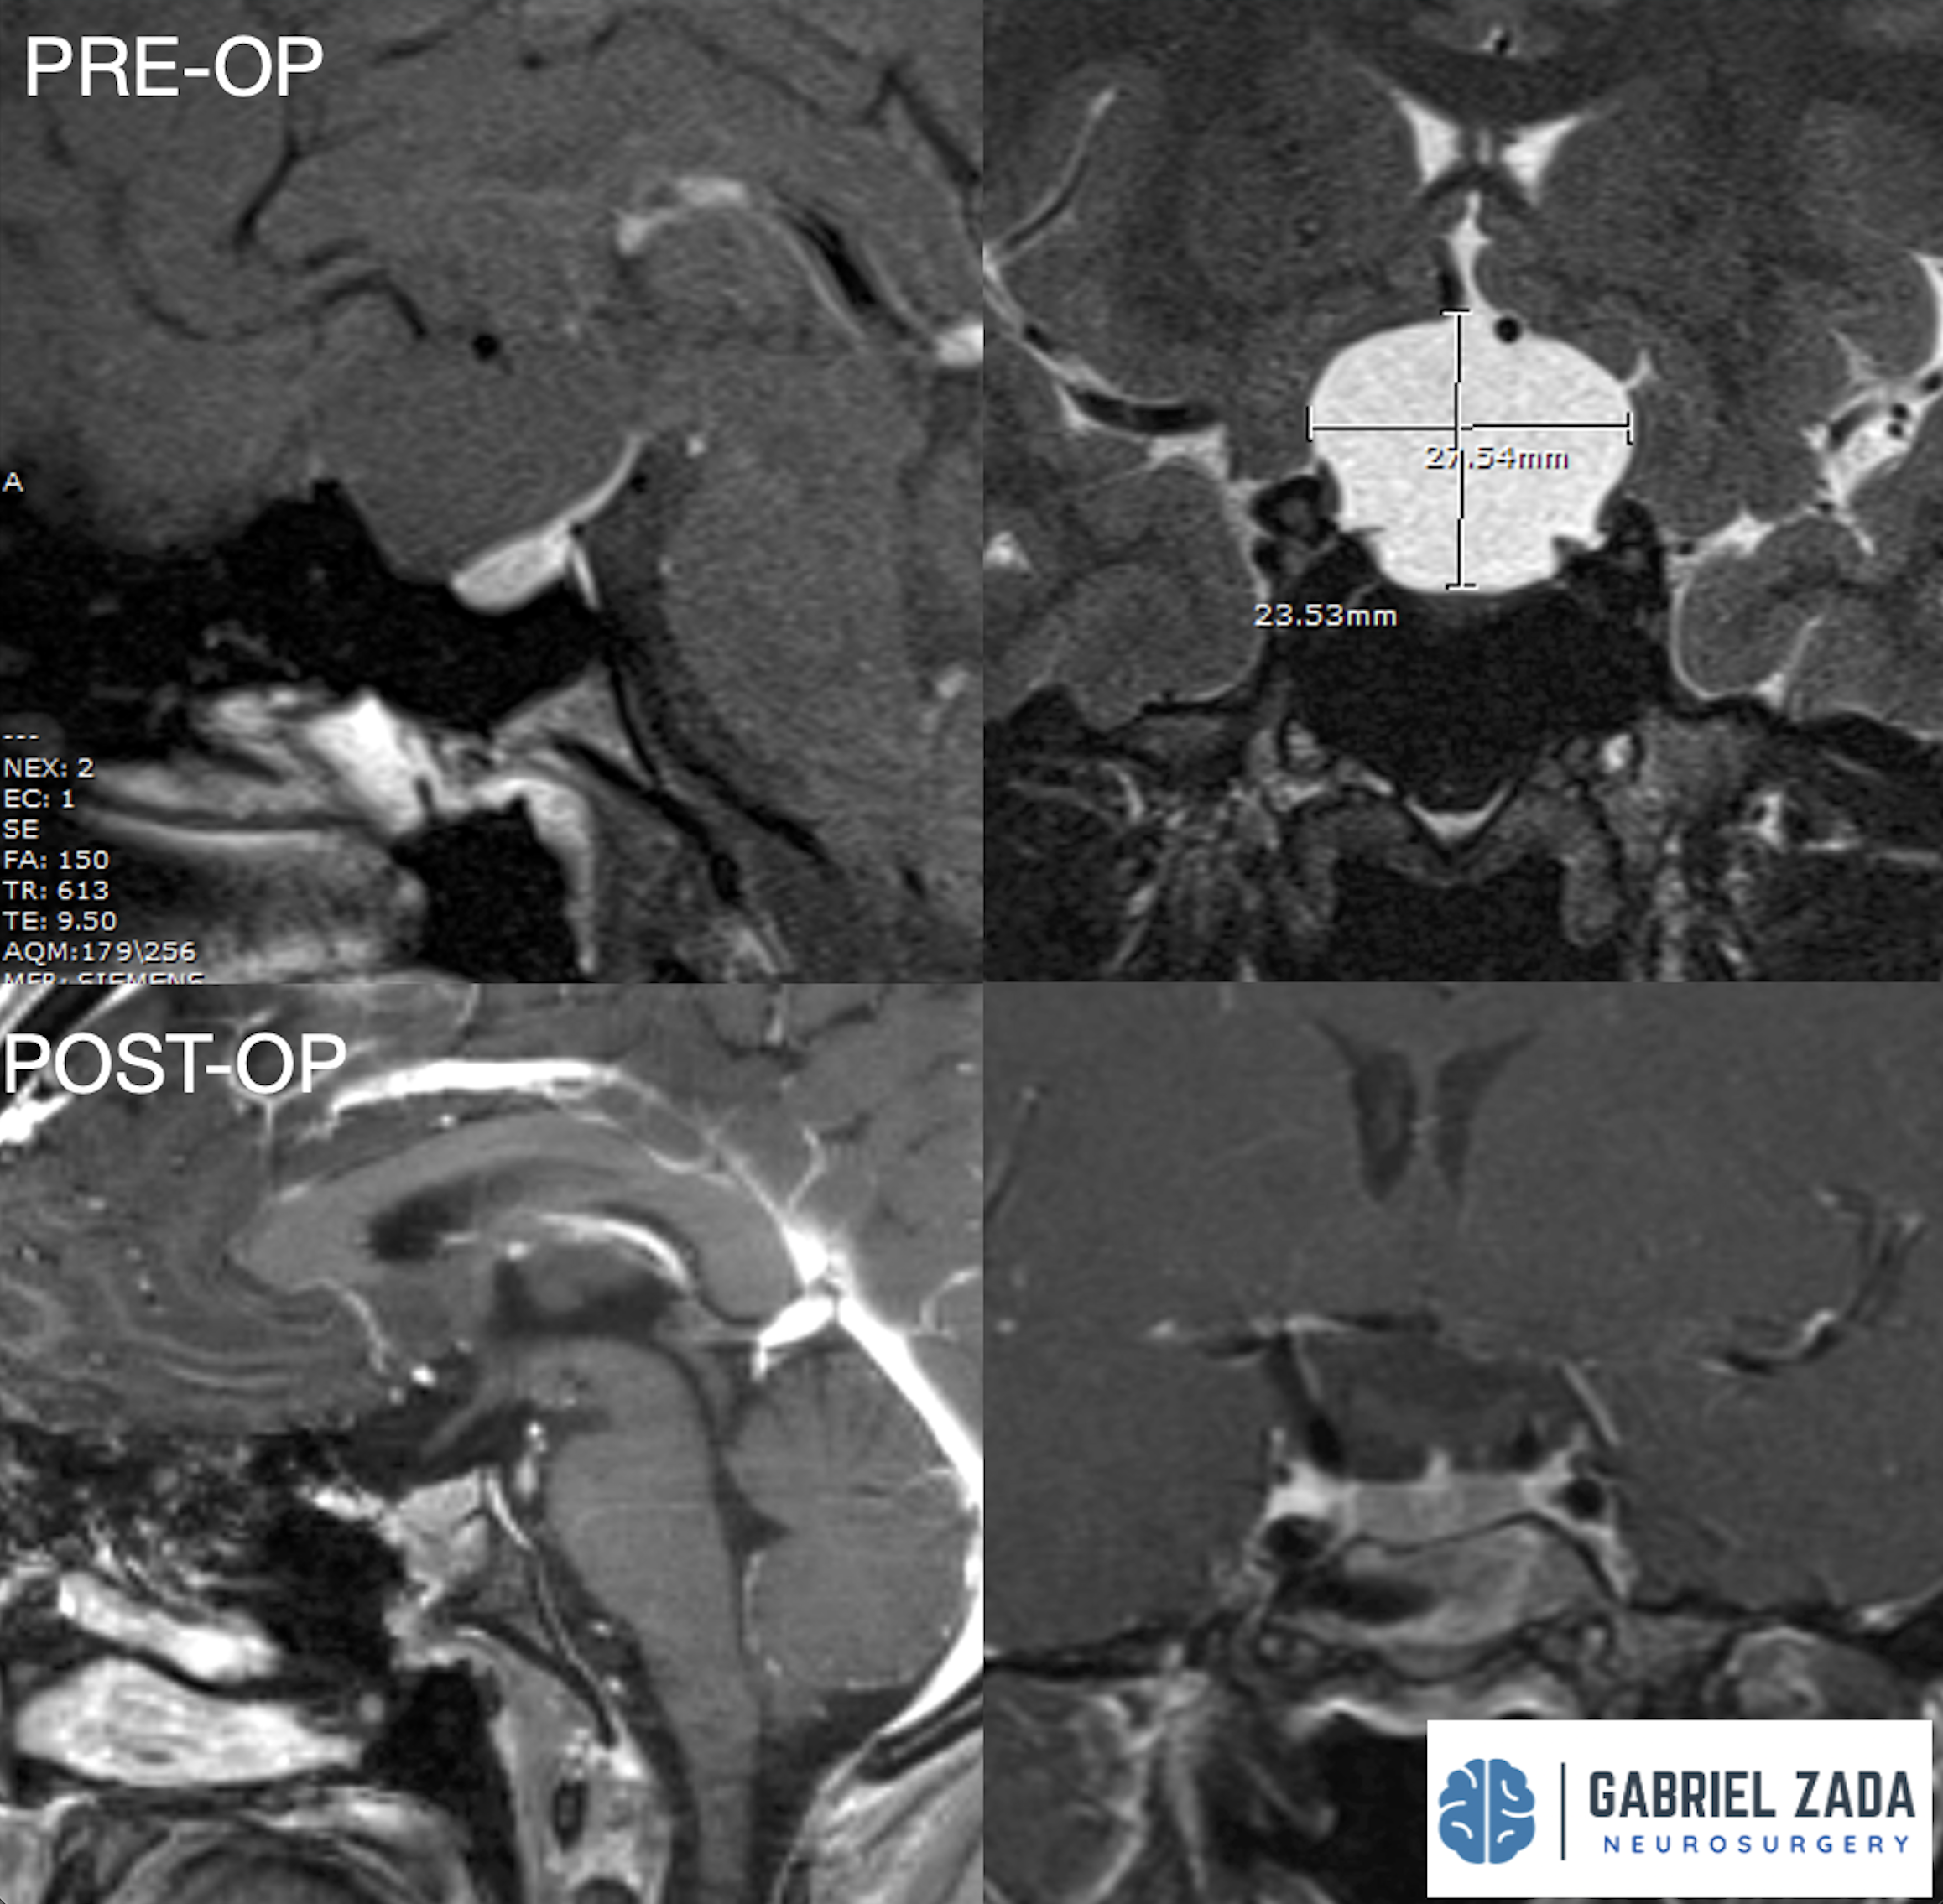

Explore this comprehensive gallery featuring pre‑ and post‑operative imaging of patients with skull‑base tumors treated by Gabriel Zada, MD, MS, FAANS, FACS. These cases highlight Dr. Zada’s expertise in advanced neurosurgical techniques and outcomes.

*Representative cases shown for educational purposes. All images de-identified. Individual results vary.